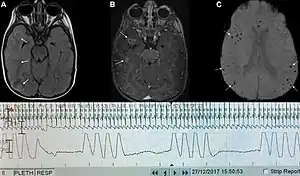

Graph showing Biot's respiration and other pathological breathing patterns.